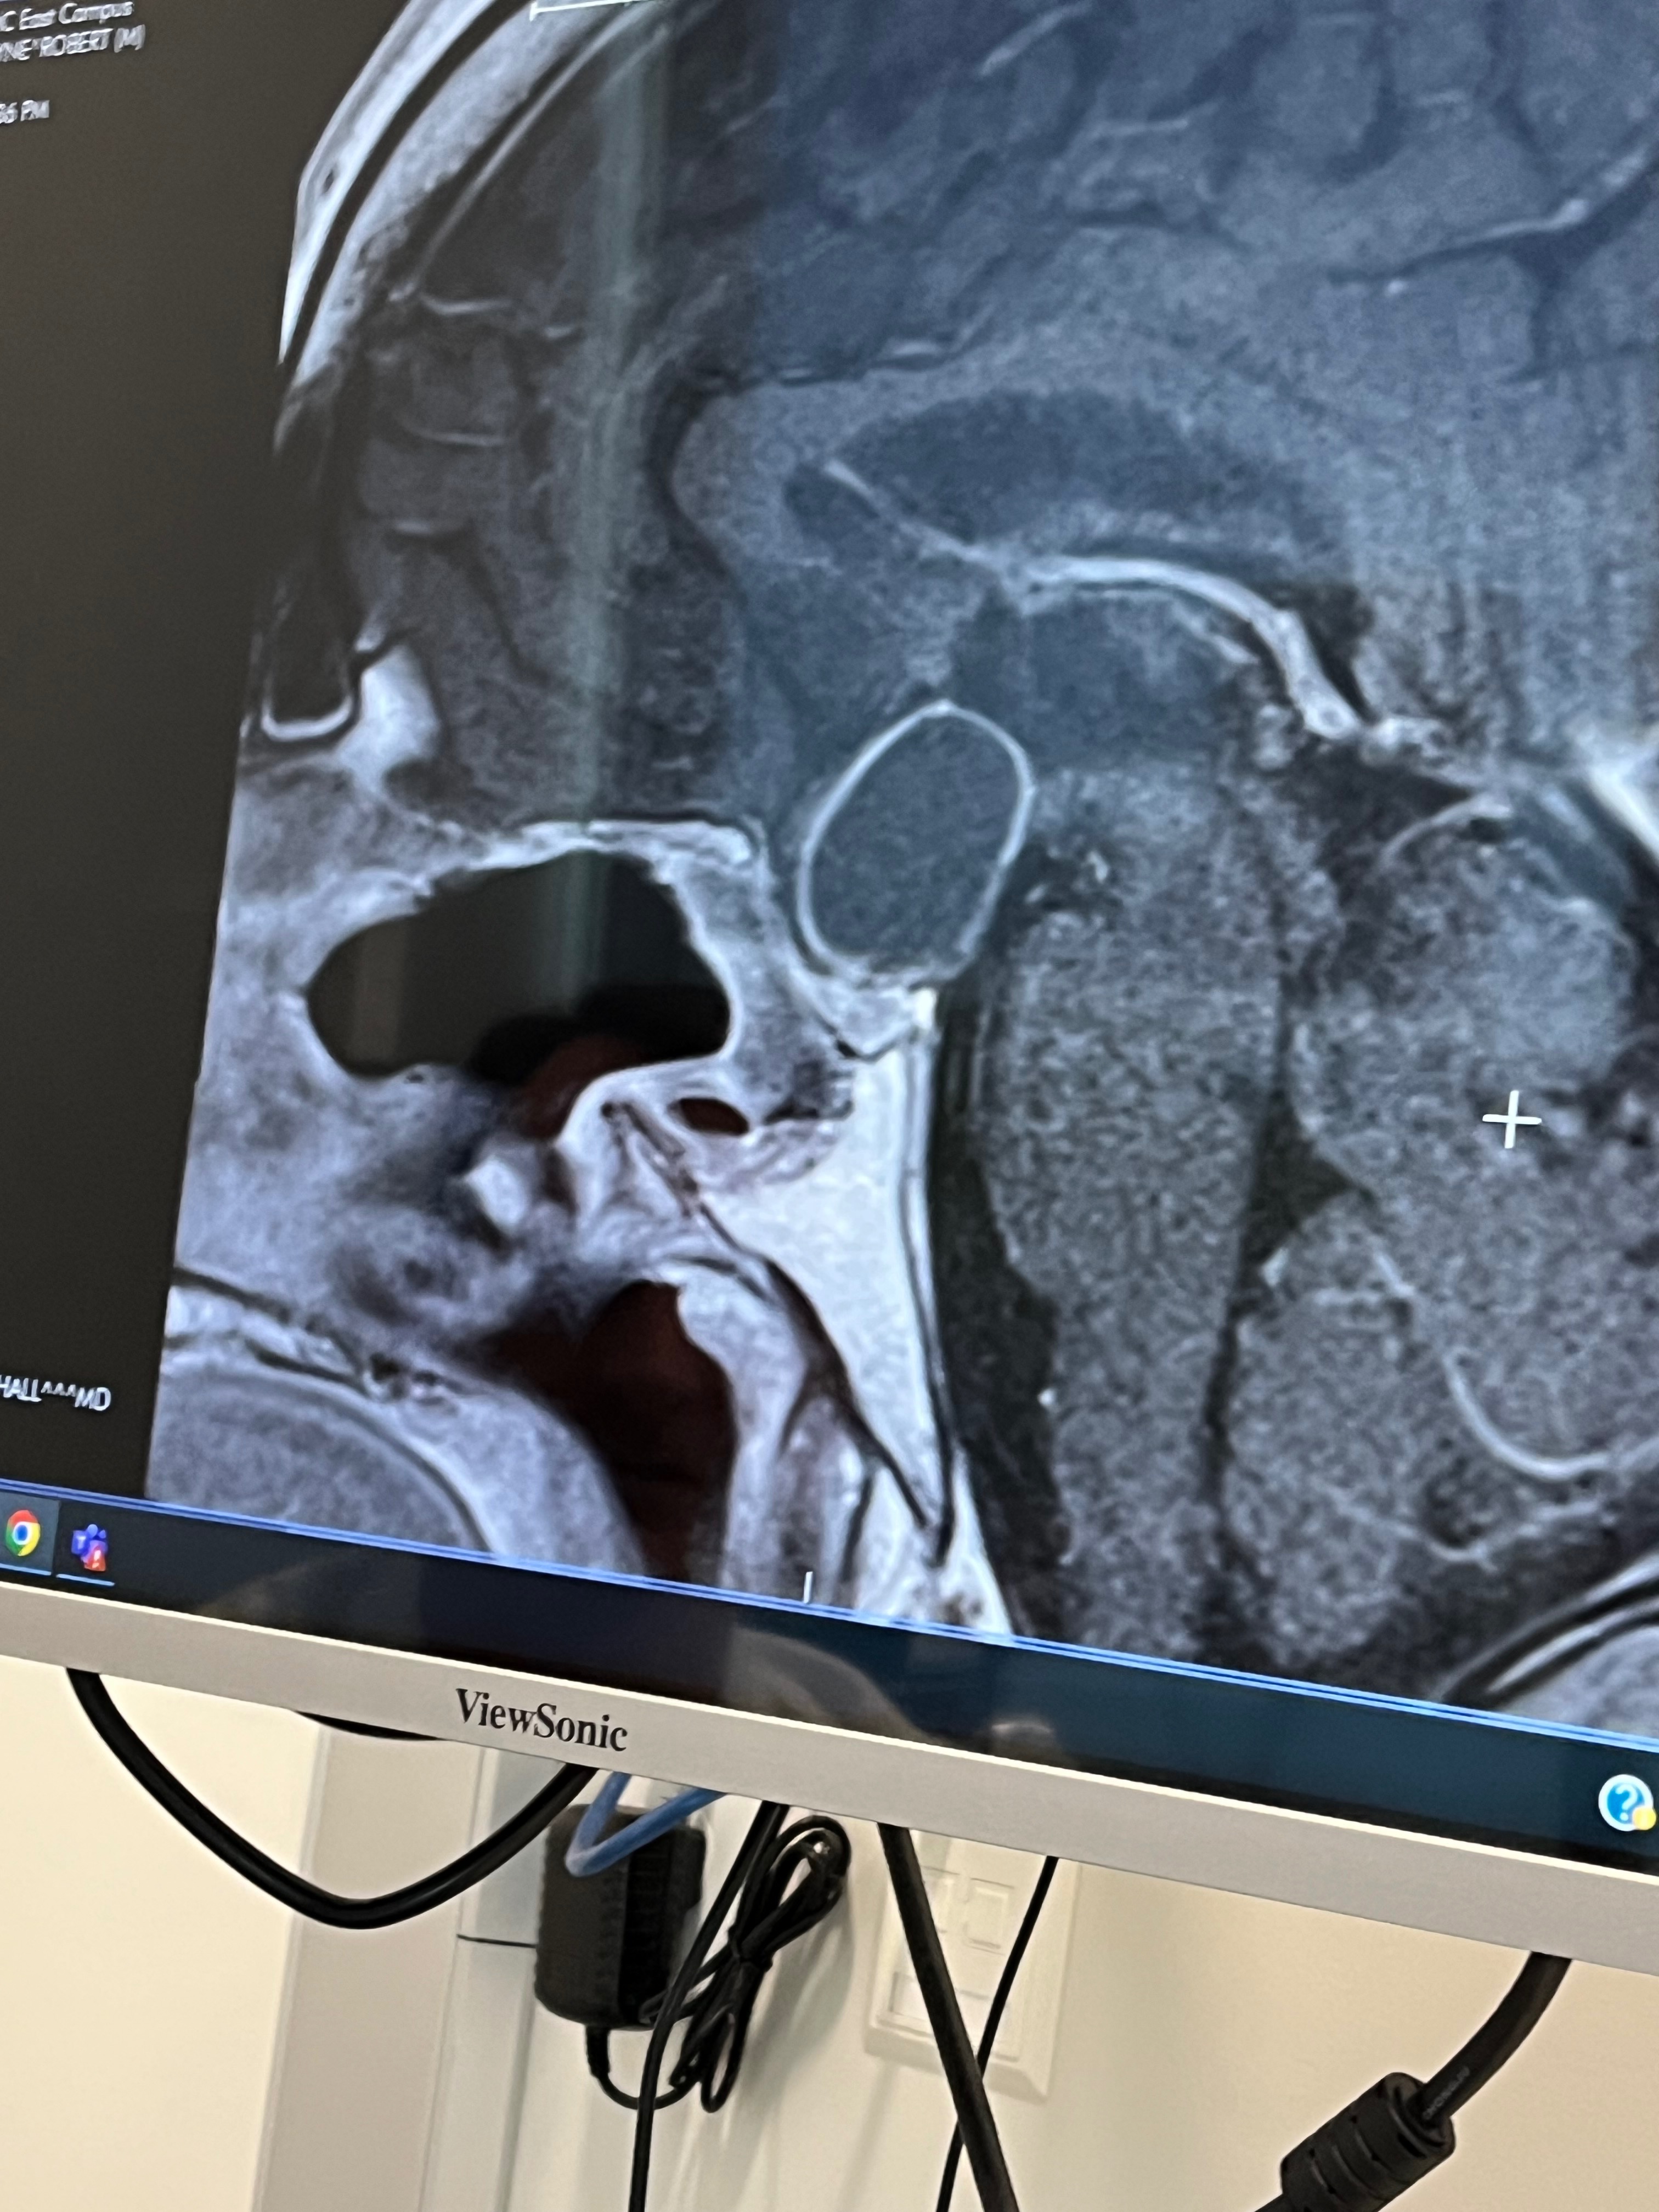

I wanted to share the story of my son Wayne Herzog. Last year in 2024 my son was suffering from intense headaches and not feeling quite normal. He trudged on and just chalked it up to weight gain and high blood pressure. However, one day he was shuffling in the store and his eyes wouldn’t focus. After a long conversation with our family nurse, we went to the ER at the VA (yes..He is a Vet!). And much to our surprise what they found was an enormous fluid filled cyst with a tumor in his brain. He was swiftly transported to a hospital where he was seen by a top surgical Neourologist. The first 24 hours were very critical as they placed tubes in his head to remove the fluid that was putting an enormous amount of pressure on his brain. The days and weeks to follow brought him through another invasive brain surgery that drained the cyst and an attempt to remove the tumor. Due to the location of the tumor they were unable to remove it all for fear it would cause him blindness. He recovered over several months and was scheduled for radiation therapy in the months to come. By late December of 2024 he had completed as much of the radiation therapy as he could, but had to stop it because the fluid filled cyst had returned and was continuing to grow. They decided to wait and watch this growth. In the meantime Wayne worked harder than ever to rehabilitate himself. We had attempted to apply for Social Security Disability ( July 2024), but the government process has denied him. May of 2025 the tumor has reached a state that has put him in danger of losing his life again. He will need yet another surgery to remove the cyst and possible chemo therapy or radiation to follow. We have been told He is still over 200 days out from any kind of approval for Social Security Disability and he is not able to sustain basic living necessities. I never dreamed I would be writing this letter to the many in an attempt to find some financial support for Wayne. He is such a kind hearted, hard working young man and a Veteran who took great pride in serving his country (For YOU and Me). If you could find it in your heart to support him in any small way I know He would be eternally grateful and blessed to have support from family and friends. Through this whole thing we have been blessed with prayers…. My prayers are that God will continue to guide Wayne through this time and provide for him as his needs arise.